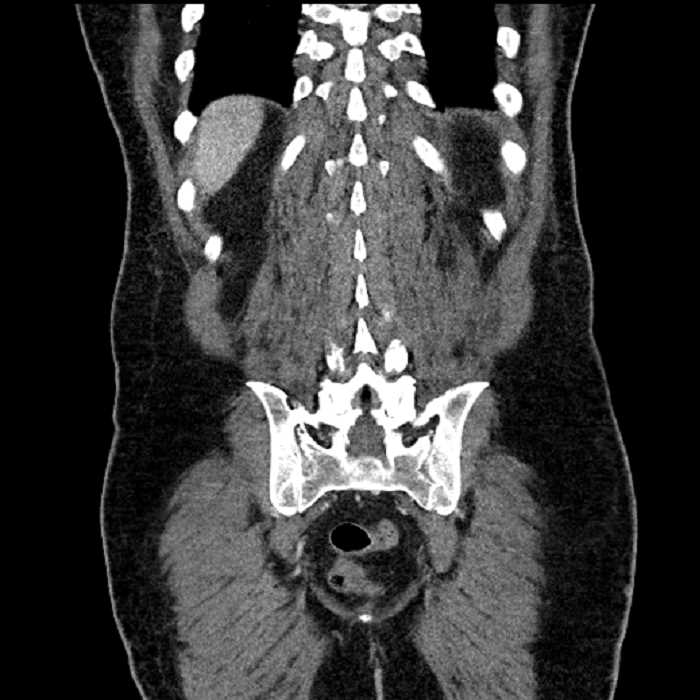

Age: 63

Sex: Male

Indication: Abdominal pain

• Large fluid density structure in hepatic segments 7 and 8 measuring 10 x 7 x 7 cm with internal septation and circumferential ill-defined low density compatible with edema

• Peripherally enhancing subcapsular collections along the anterior margin of the left hepatic lobe measuring 3 x 1 cm and 2 x 1 cm

• Clearly marginated fluid density structure in segment 7 and several other scattered tiny hypodensities, which likely represent cysts

• Mild mural thickening of a segment of the sigmoid colon with adjacent fat stranding and a 1.5 cm fluid and gas collection along the tip of an inflamed diverticulum

• Loss of the normal fat plane between this collection and adjacent loops of small bowel, which demonstrate mural thickening

Acute sigmoid diverticulitis complicated by a small contained perforation and a large abscess in the right hepatic lobe. Additional small subcapsular abscesses along the anterior margin of the left hepatic lobe.

Additionally, loss of the normal fat plane between the peridiverticular collection and adjacent thickened loops of small bowel raises the potential for an enterocolonic fistula.

High grade stenosis of the left common iliac artery. The left external and internal iliac arteries are patent.

Hepatic abscess showing the double target sign with low density internally surrounded by a thin inner enhancing rim (red arrow) and ill-defined outer low density rim (yellow arrow). Blue arrow indicates an internal septation. Red arrows: additional smaller subcapsular abscesses. Red arrow: focal contained perforation associated with diverticulitis.